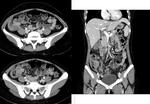

44세 여자 환자로 내원 3주 전부터 발생한 발열 및 1주 전부터 발생한 설사를 주소로 내원하였다. 최근 여행력은 없었으며, 과거력에서 특이 소견은 관찰되지 않았으나, 3주 동안 약 3 kg 정도의 체중 감소를 호소하였다. 이학적 검사에서 혈압 110/70 mmHg, 심박동 94회/분, 체온 38.3 oC 였고, 혈액 검사에서 WBC 2,900/mm3, Hb 11.4 g/dL, platelet count 152,000/mm3 이었고, albumin 3.4 g/dL, AST/ALT 68/49 IU/L, LDH 835 IU/L, CRP 10.1 mg/dL (참고치 < 0.5) 이었다. 복부 전산화 단층 촬영술(그림 1)을 시행하였고, 대장내시경(그림 2)을 시행하였으며, 조직 검사에서 그림 3과 같은 소견이 관찰되었다. 진단은?